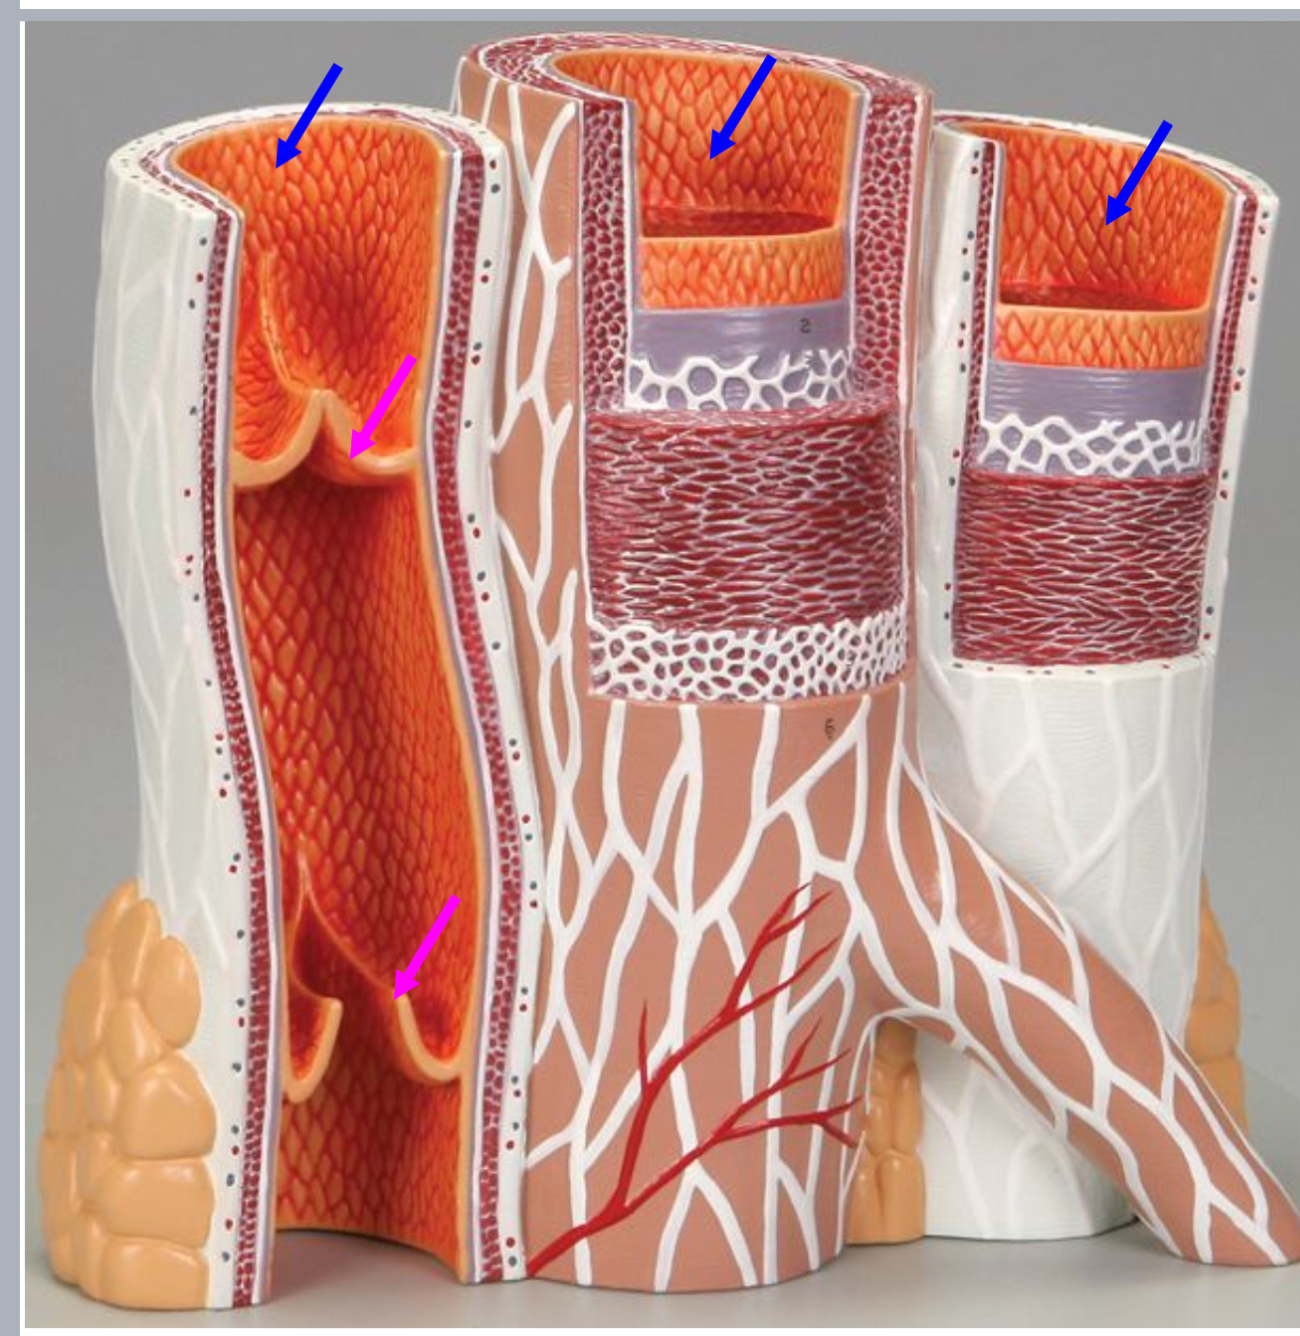

Tunica intima

Name the blue arrow

Lines lumen and release vasoactive chemicals

Function of tunica intima

Venous valves

Name the pink arrow

Prevent backflow of blood

Function of venous valves